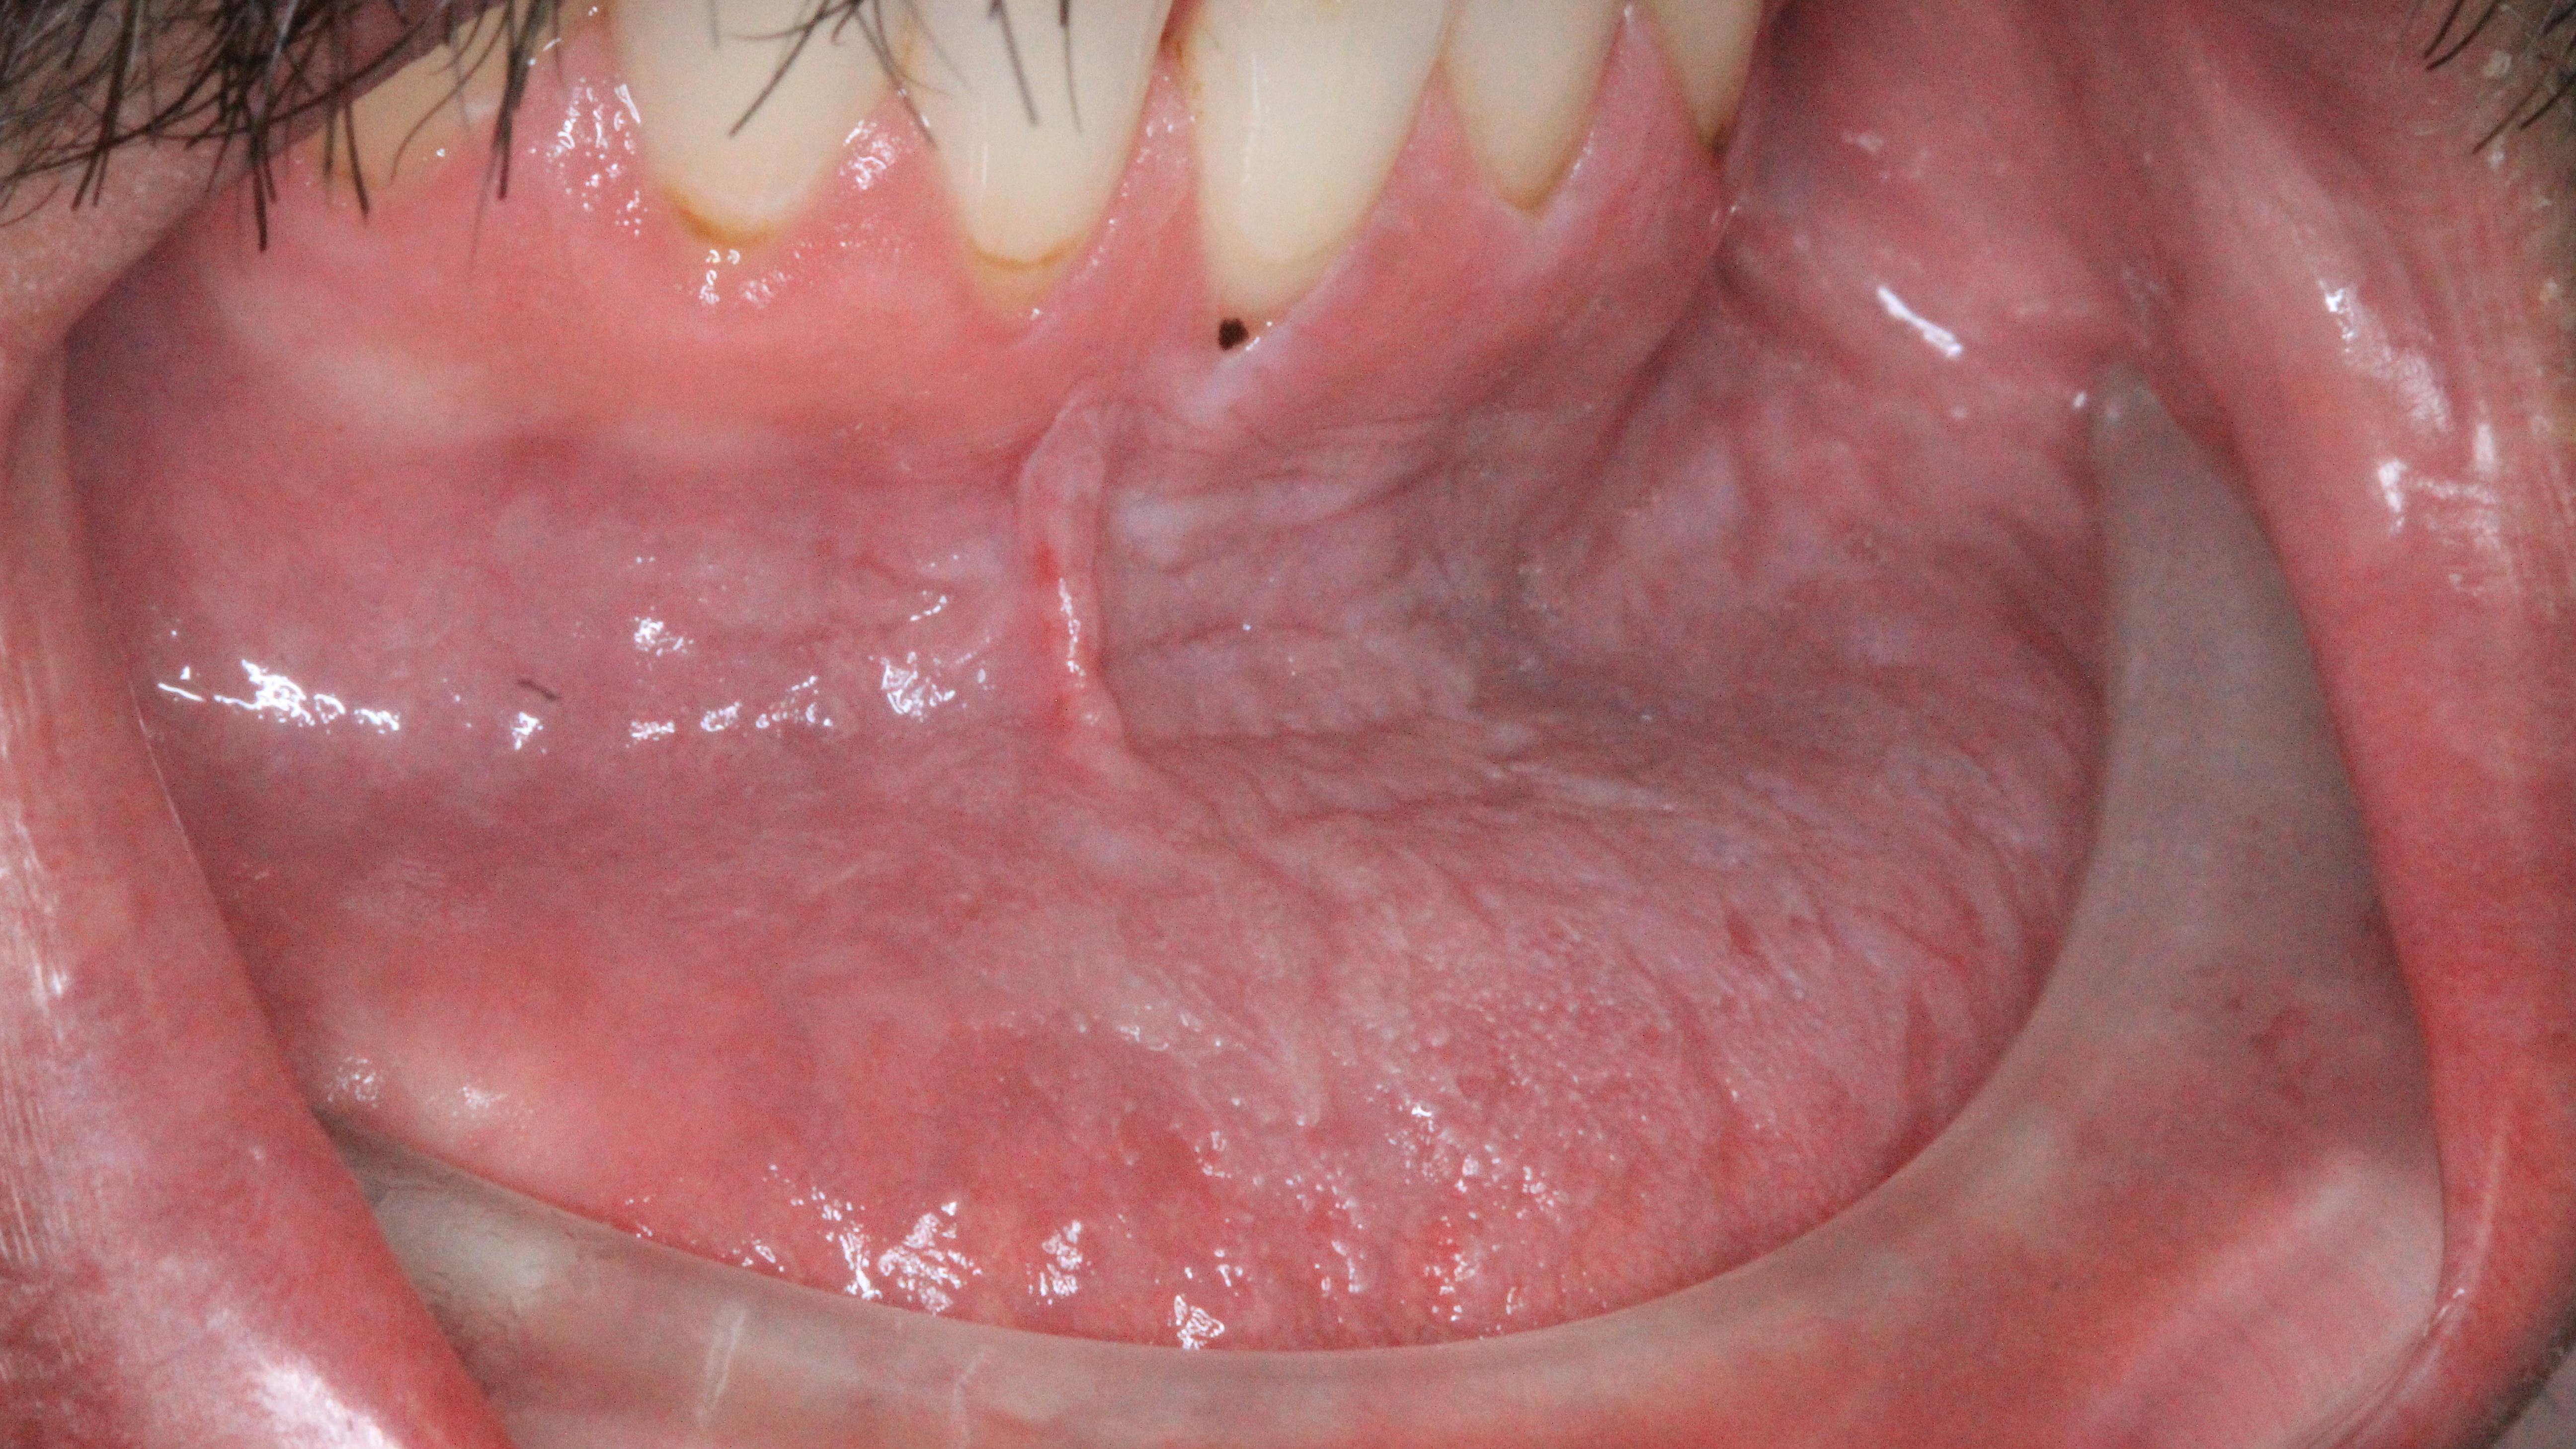

His abscess was addressed, and an assessment of the tissue followed. Upon palpation, a large area of the lower left vestibule was noted to have rough, corrugated-cardboard-like tissue.

“The oral lesions seen in smokeless tobacco use may be white lesions, red and white plaques, or raised red or white lesions. These may be precancerous, in situ carcinomas, squamous cell carcinomas, or verrucous carcinomas, predominantly occurring at the mucosal location where the quid is placed.”2